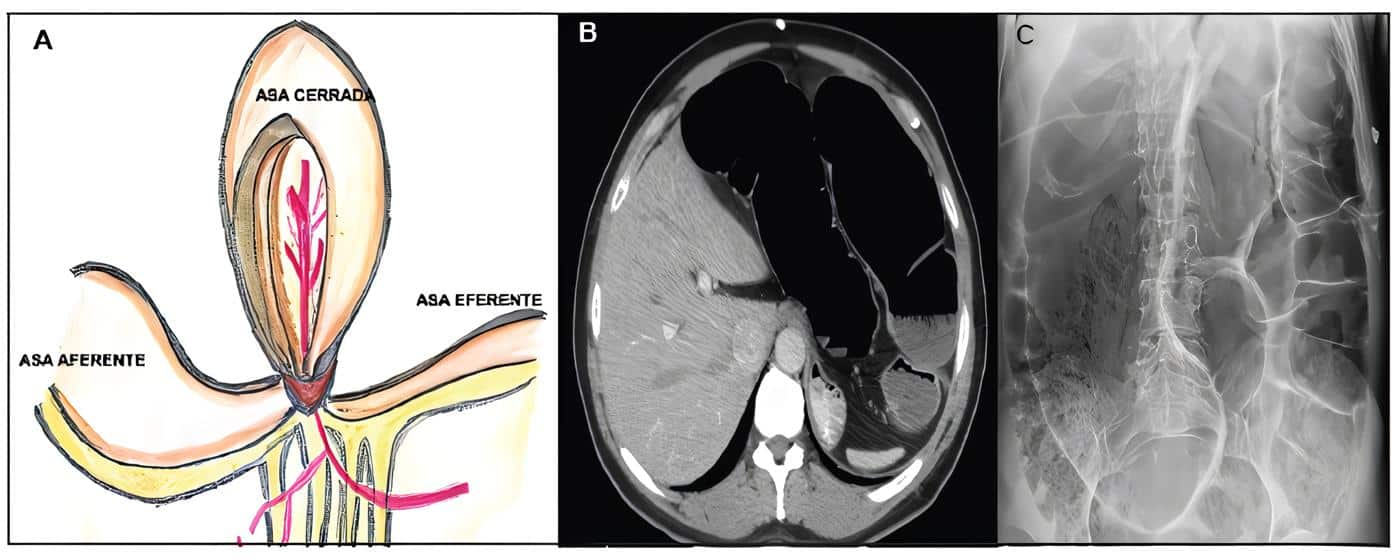

La figura 1 ilustra una representación esquemática y radiológica de una obstrucción intestinal en asa cerrada.

Figura 1. Representación esquemática y radiológica de obstrucción en asa cerrada. A. En la obstrucción en asa cerrada el lumen intestinal es obstruido en dos sitios localizados uno cerca al otro en los puntos de entrada y salida del asa; B. Corte axial de una tomografía de abdomen de un paciente con diagnóstico de vólvulo del sigmoide; C. Radiografía de abdomen de paciente con obstrucción intestinal con relación a vólvulo del sigmoide, se evidencia importante distensión de asas intestinales. Fuente: Elaboración propia de los autores.